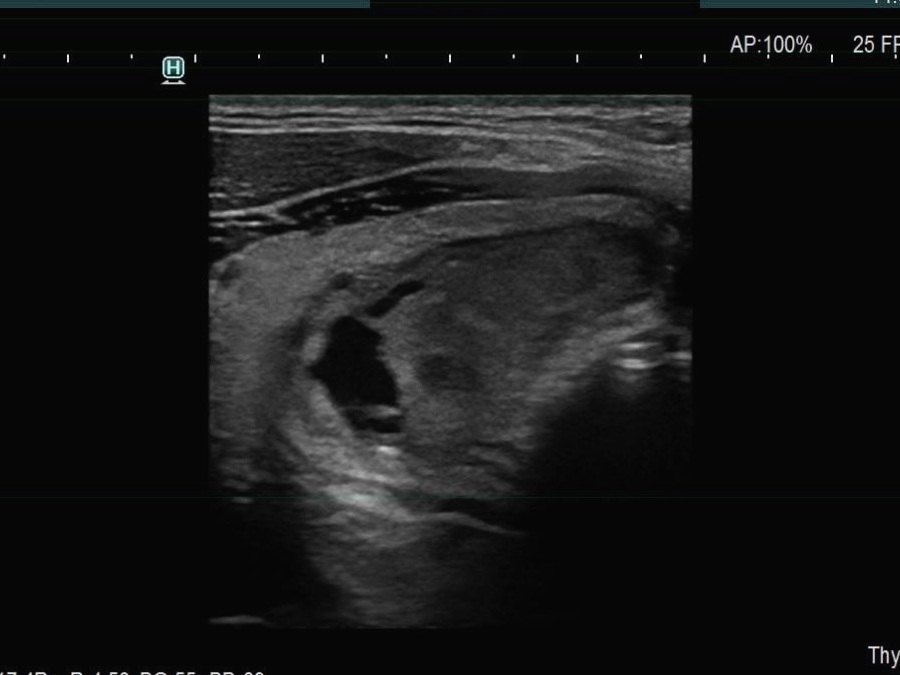

Ultrasonography. The thyroid was echonormal. There were multiple smaller lesions in the right lobe. The largest one was minimally hypoechoic and presented with halo and perinodular vascularity. A large, hypoechoic nodule occupied almost the entire left lobe. The nodule had lobulated and spiculated margins and bulged into the sternocleidomastoid muscle. The vascularity was not specific.

FNA of the left nodule resulted in papillary cancer.

Total thyroidectomy and left lymphadenectomy was performed. Histopathology disclosed papillary cancer according to the nodule in the left lobe. Gross extrathyroidal extension was found into the adipose tissue and the strap muscle.